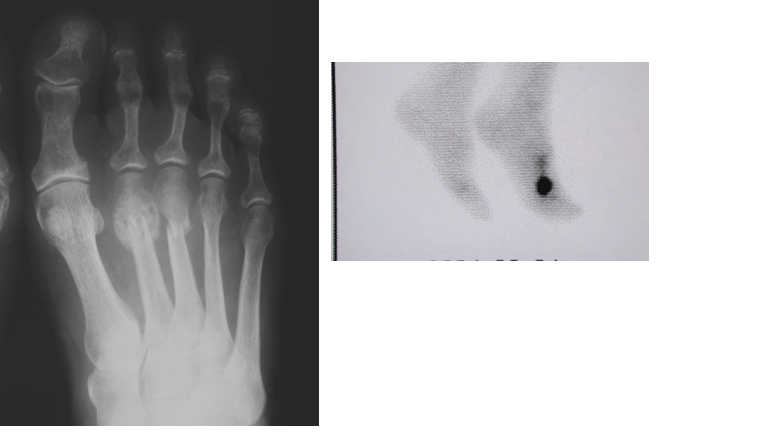

Przedstawiony radiogram oraz scyntygrafia stopy w projekcji AP 34-letniego mężczyzny wykazuje: